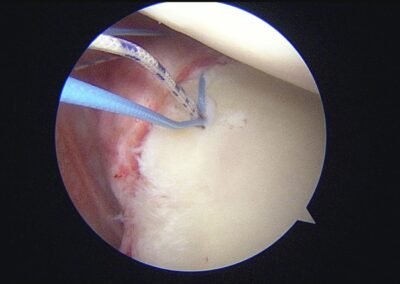

GalleryShoulder rotator cuff repair Meniscus root repair Meniscus repair Bankart repair for recurrent shoulder dislocation ACL reconstruction Machines Instruments